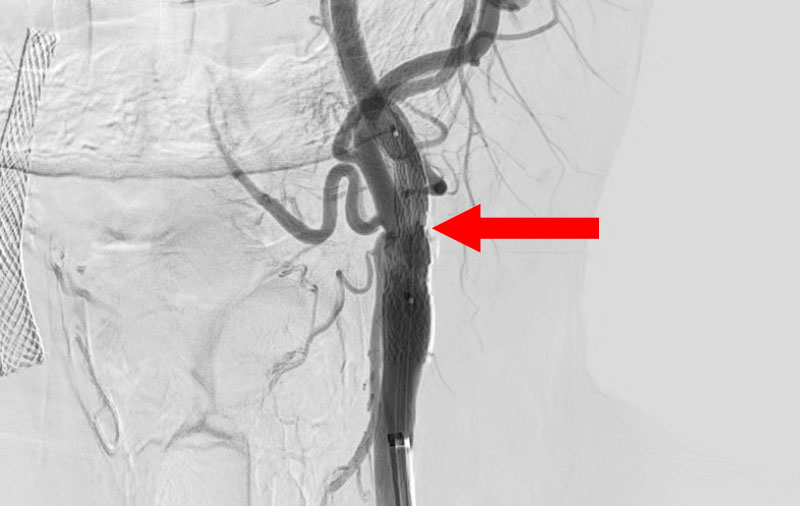

'25年10月

左総頚動脈狭窄症

30代

院内外来

No.1590 手術前

No.1590 手術中

No.1590 手術後